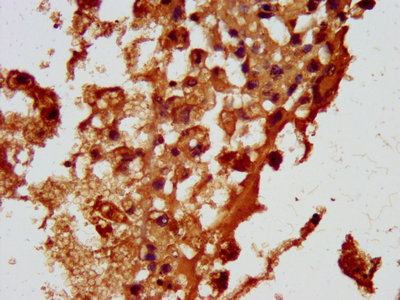

ApplicationELISA, IHC, IF; Recommended dilution: IHC:1:20-1:200, IF:1:20-1:200